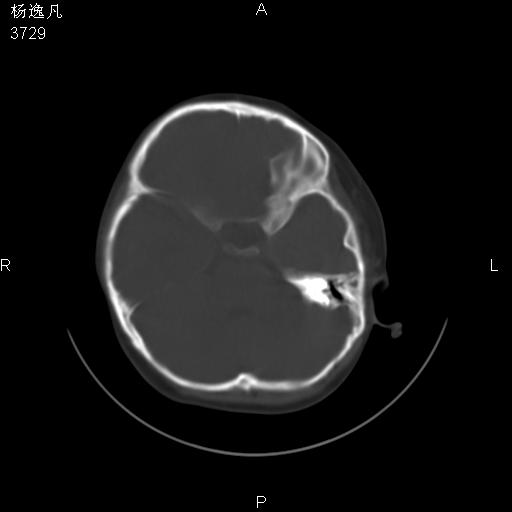

男性,5岁,面部受外伤,余无特殊

骨窗

1、右面部及颞部软组织肿胀。

头颅ct平扫未见明确外伤性征象,右侧面部及颞部软组织肿胀,后鼻腔软组织影增大,增厚,鼻咽顶部变窄,考虑鼻咽腺样体增值肥厚。

双侧位置太不对称,未见明显骨折征象。